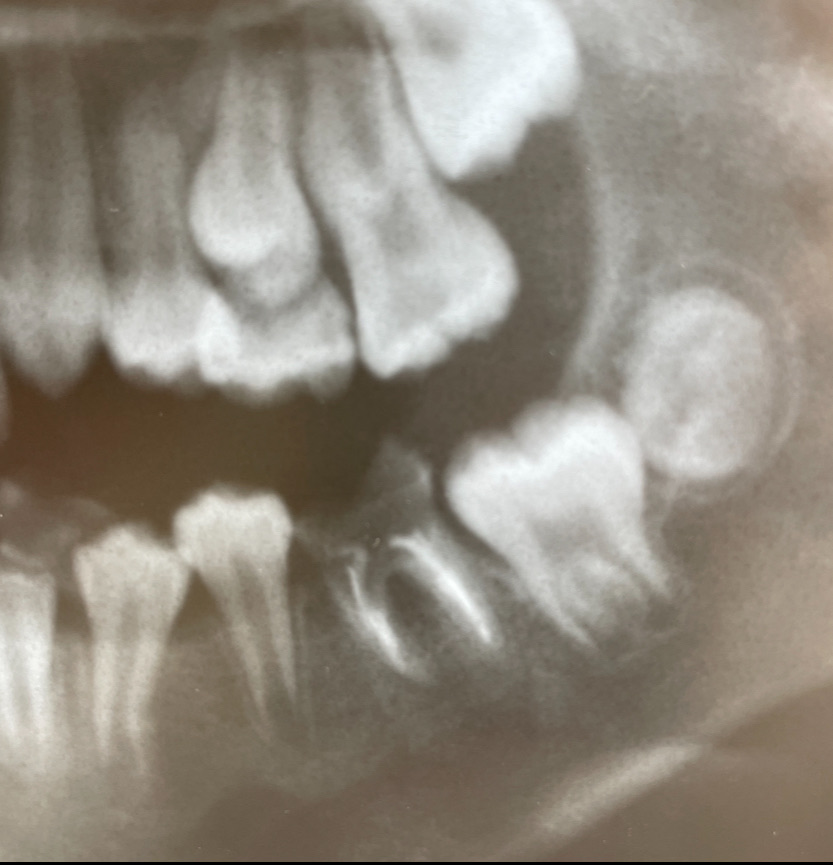

こちらの写真は、10才女の子のレントゲン写真です。

下顎の6歳臼歯に、虫歯ができています。

虫歯の状態は、歯槽骨よりも深く、治療することが不可能な状態です。

この歯の一つ後ろに存在する第二大臼歯は、もうまもなく萌出(ほうしゅつ)すると予想されます。